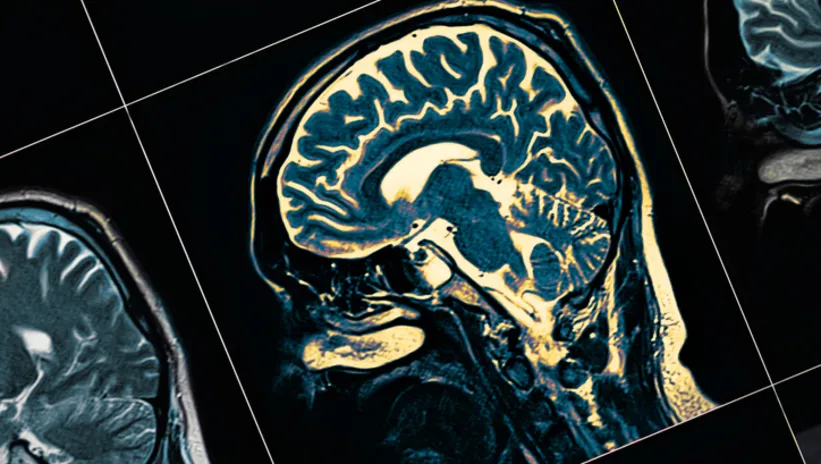

İlk olarak hastanın hikayesi,genel ya da nörolojik muayenesi yapılır. Daha sonra Beyin tomografisi ve beyin manyetik rezonans görüntülemeden faydalanılır.Bu testler sayesinde beyin tümörü yerleşimi, cinsi, hakkında ve büyüklüğü ile ilgili çabuk ve kısa zamanda bilgi alınır.Bazı beyin tümörleri teşhisinde ise beyin biopsisi gereklidir.